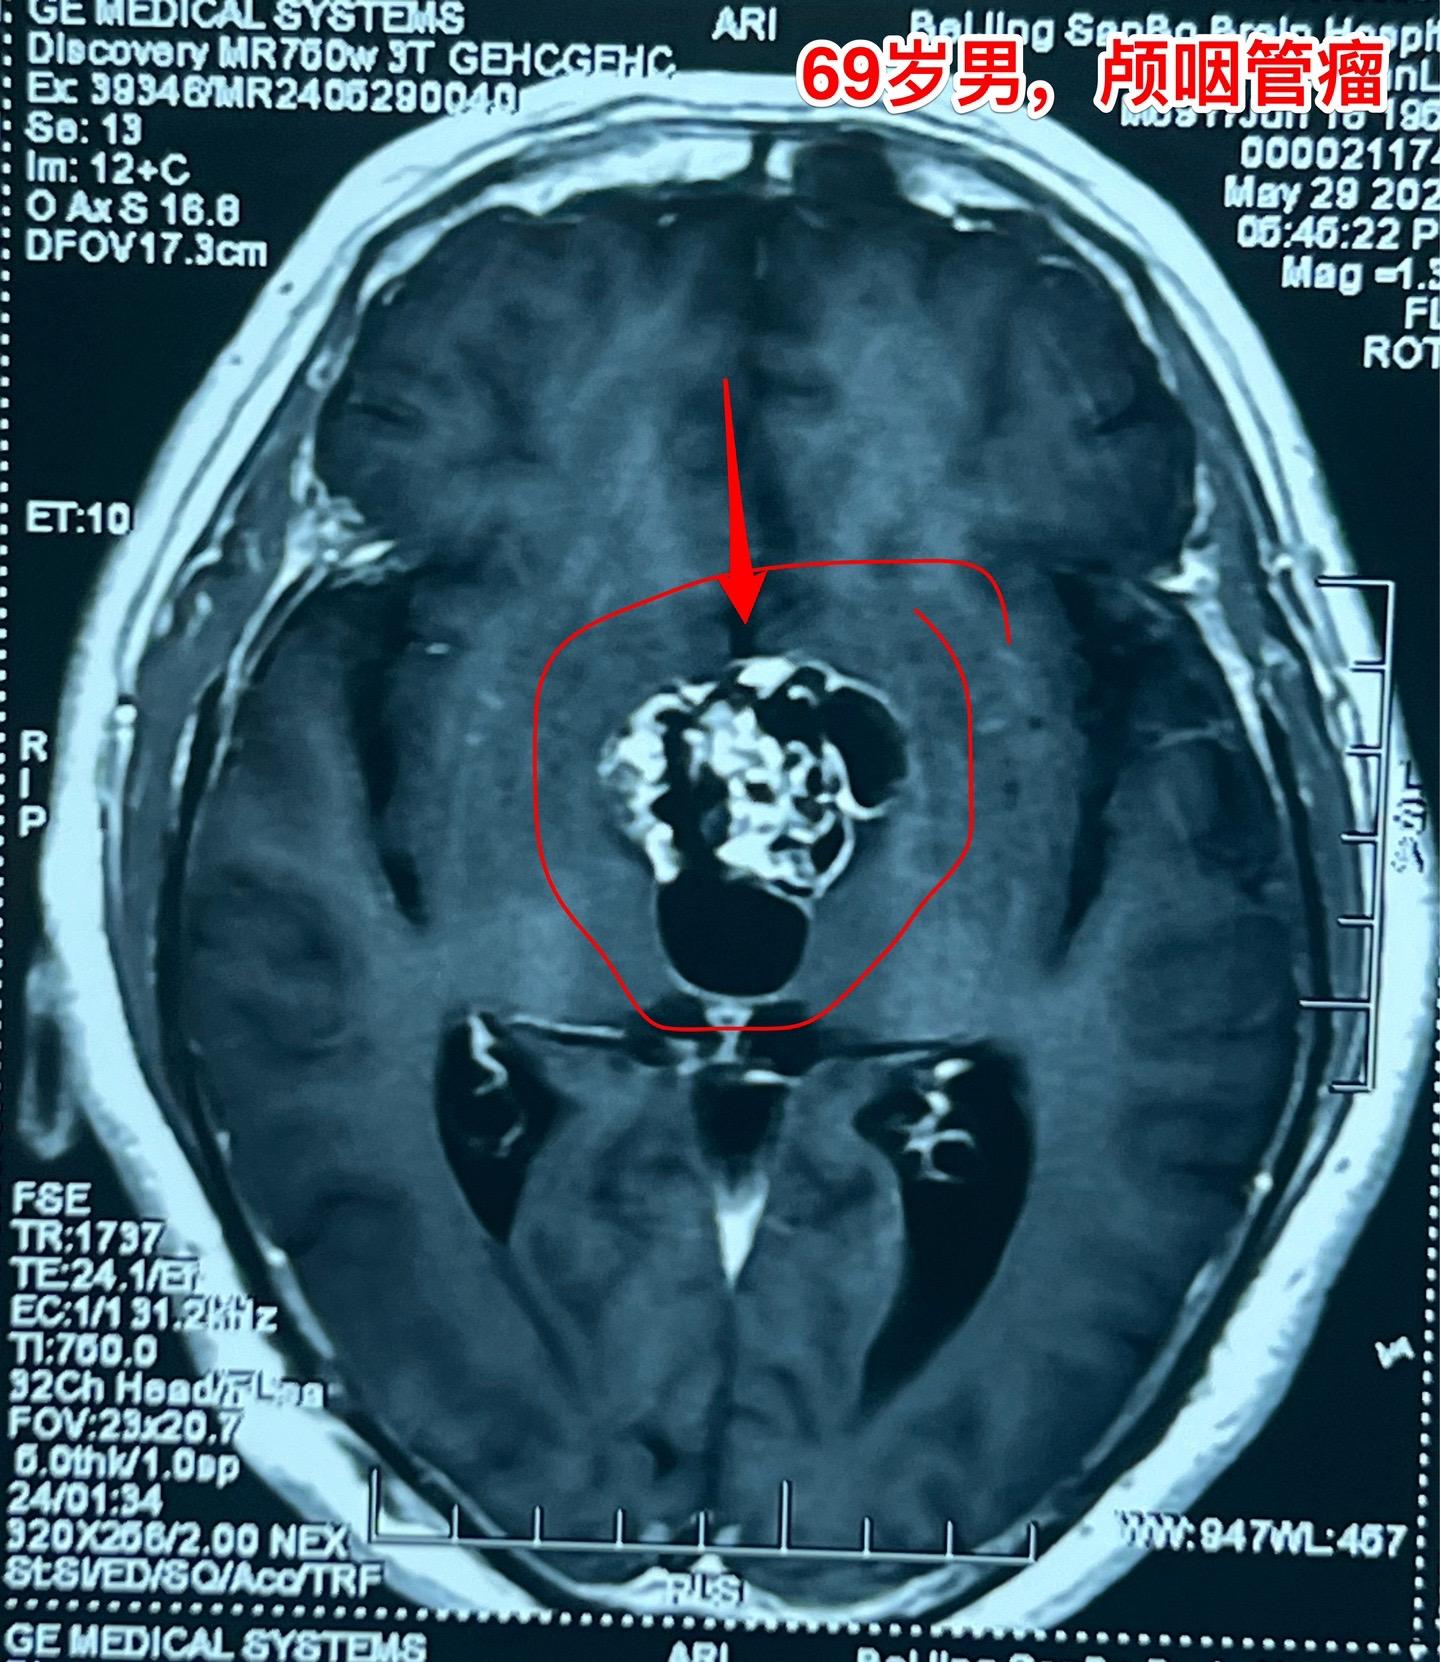

69岁发现颅咽管瘤还能作手术吗?69岁的南通市老人近半年出现记忆力差、糊涂。4月份出现尿失禁,到医院检查才发现病根儿是颅咽管瘤,肿瘤体积大,导致了脑积水。第一步在当地医院先作了脑室-腹腔分流术,治疗脑积水,尿失禁的症状有改善。 但是老人的身体很虚弱。还不能下地行走。这样的身体状态是不能承受切除颅咽管瘤这样的大手术的。 老人的女儿随后和我加后,我给予老人补充激素后,老人的身体状况才逐步改善,慢慢地能下地走路了。 不能不佩服这家人的勇气和爱心[强][强]!